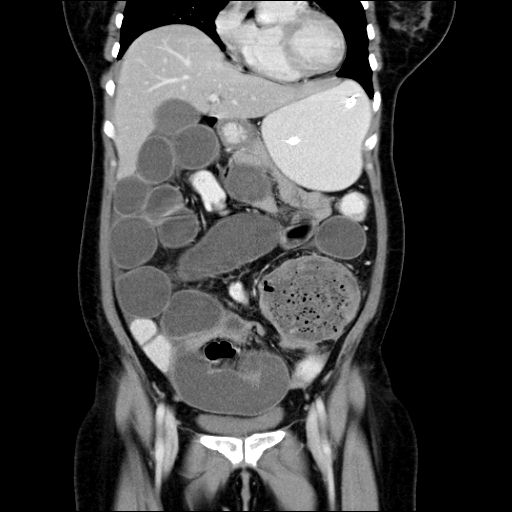

There was diffuse hypodensity seen involving the brainstem and a mass was suspected. The brainstem was also expanded.

The MRI revealed a diffuse non enhancing mass involving the pons mainly with expansion of the pons and compression of the surrounding cisterns.

It was diagnosed as a case of Diffuse Pontine Glioma.